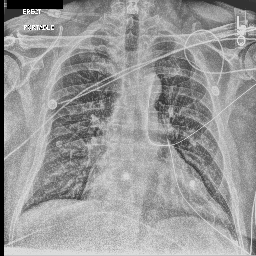

Evaluation of Generated Reports

Ground Truth TieNet Ours (full)

[Uncaptioned image] cardiomegaly is moderate. bibasilar atelectasis is mild. there is no pneumothorax. a lower cervical spinal fusion is partially visualized. healed right rib fractures are incidentally noted. ap portable upright view of the chest. there is no focal consolidation, effusion, or pneumothorax. the cardiomediastinal silhouette is normal. imaged osseous structures are intact. pa and lateral views of the chest. there is mild enlargement of the cardiac silhouette. there is no pleural effusion or pneumothorax. there is no acute osseous abnormalities.

[Uncaptioned image] the course of the dobbhoff feeding catheter is unremarkable, and its tip is seen projecting over the stomach. there is no evidence of complications, specifically no pneumothorax. as compared to the prior radiograph dated DATE, there has been no other significant interval change. ap portable upright view of the chest. overlying ekg leads are present. there is no focal consolidation, effusion, or pneumothorax. the cardiomediastinal silhouette is normal. imaged osseous structures are intact. as compared to the previous radiograph, there is no relevant change. the endotracheal tube terminates approximately 3 cm above the NAME. the endotracheal tube extends into the stomach. there is no evidence of complications, notably no pneumothorax. there is no pleural effusion or pneumothorax.

Table 4: Sample images along with ground truth and generated reports. Note that upper case tokens are results of anonymization.

Table 4 demonstrates the qualitative results of our full model. In general, our models are able to generate descriptions that align with the logical flow of reports written by radiologists, which start from general information (such as views, previous comparison), positive, then negative findings, with the order of lung, heart, pleura, and others. TieNet also generates report descriptions with such logical flow but in slightly different orders. For the negative findings cases, both our model and TieNet do well on generating reasonable descriptions without significant errors. Regarding the cases with positive findings, TieNet and our full model both cannot identify all radiological findings. Our full model is able to identify the major finding in each demonstrated case. For example, cardiomegaly in the first case, pleural effusion, and atelectasis in the second case.

A formerly practicing clinician co-author reviewed a larger subset of our generated reports manually. They drew several conclusions. First, our full model tends to generate sentences related to pleural effusion, atelectasis, and cardiomegaly correctly—which is aligned with the clinical finding scores in Table 3. TieNet instead misses some positive findings in such cases. Second, there are significant issues in all generated reports, regardless of the source model, which include the description of supportive lines and tubes, as well as lung lesions. For example, TieNet is prone to generate nasogastric tube mentions while our model tends to mention tracheostomy or endotracheal tube, and yet both models have difficulty identifying some specific lines such as chest tube or PICC line. Similarly, both systems do not generate the sentence with positive lung parenchymal findings correctly.

From this (small) sample, we are unable to draw a conclusion whether our model or TieNet truly outperforms the other since both present with significant issues and each has strengths the other lacks. Critically, neither of them can describe the majority of the findings in the chest radiograph well, especially for positive cases, even if the quantitative metrics demonstrate the reasonable performance of the models. This illustrates that significant progress is still needed in this domain, perhaps building on the directions we explore here before these techniques could be deployed in a clinical environment.